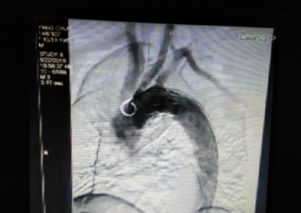

我院成功開展市屬醫(yī)院首例先心病介入封堵術(shù)?不用開刀,不會在體表留下疤痕,只需進(jìn)行局部皮膚麻醉,通過穿刺右側(cè)股靜脈插入一根幾毫米的導(dǎo)管,將封堵器送至缺損部位釋放,先天性心臟病就得到了根治。不久前,15歲的小章在我院成功接受了先天性心臟病介入封堵術(shù),他的心臟結(jié)構(gòu)和功能恢復(fù)了正常,學(xué)習(xí)和生活也得到了恢復(fù)。...